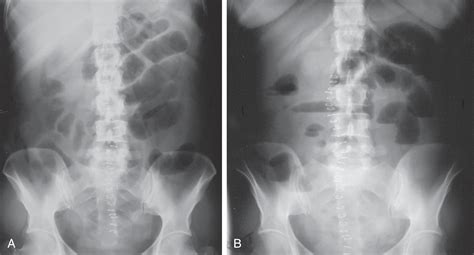

Feature Nonobstructive Pattern Obstructive Pattern

Gas Distribution Scattered throughout the small and large bowel. Localized to specific, dilated segments.

Bowel Diameter Within normal physiological limits. Significantly dilated (swollen).

Gas-Fluid Levels Minimal or absent. Prominent, indicating trapped air and liquid.

Clinical Implication Usually benign/functional issue. Requires immediate medical intervention.